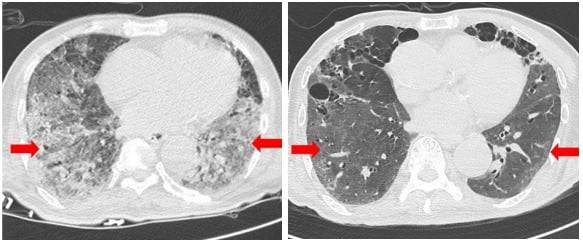

연구진은 치료제 투여 106일 후 흉부 컴퓨터단층촬영(CT)을 진행했다. 그 결과 간유리음영(GGO)과 경화 정도가 감소하고, 오른쪽 폐 상단에 위치한 결절의 크기가 감소하는 등 폐 기능 개선을 확인했다. 줄기세포 치료제가 코로나19로 인한 ARDS 환자의 치료에 도움이 될 수 있음을 확인했다는 설명이다.